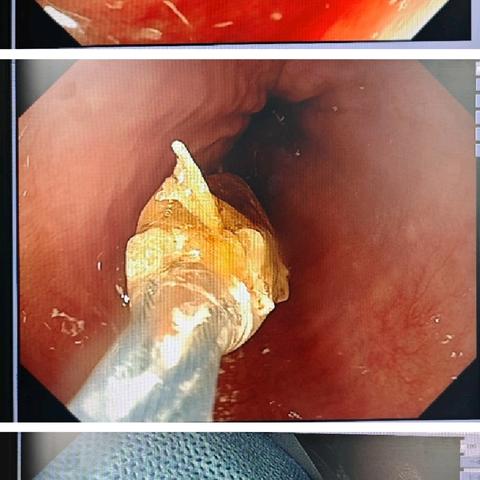

枣核虽小,能伤脏腑;胃镜妙手,化险为夷——24小时内镜急救,守护消化道安全!